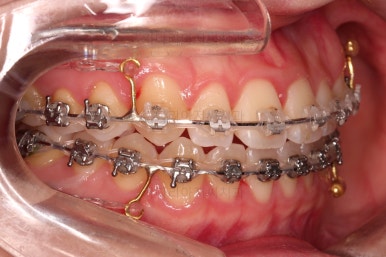

4. 치료 진행 상황

부산치아교정잘하는곳 키다리아저씨치과에서 사용한 장치는 엠파워라고 하는 자가결찰 장치인데요.

이번 환자분은 윗니는 세라믹, 아랫니는 메탈로 선택을 하셨습니다.

웃을 때 더 많이 보이는 부분은 좀 더 심미적인 세라믹으로 하고, 아랫니는 메탈도 상관없다고 하여 조합해서 사용했는데요.

동일한 회사의 동일한 규격의 장치라 혼용해서 써도 무방합니다.

장치 부착한지 얼마 안되어 치열은 매우 고르게 되었는데요.

치료 목표는 그것 뿐만 아니라 입을 조금이라도 넣고, 앞니 각도도 개선해야 되었으므로 사랑니는 모두 뽑아내고 미니스크류를 활용해서 뒤로 뒤로 밀어넣습니다.